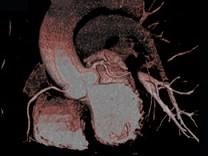

上面一组图像考虑为 ( )A、左前降支钙化B、左旋支钙化C、正常的左前降支D、右侧冠状动脉钙化E、正常的右侧冠状动脉

问题 上面一组图像考虑为 ( )

选项 A、左前降支钙化 B、左旋支钙化 C、正常的左前降支 D、右侧冠状动脉钙化 E、正常的右侧冠状动脉

答案 A